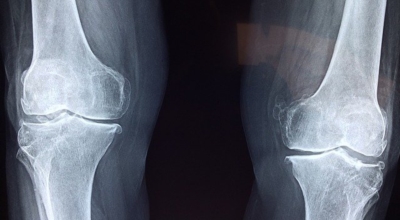

4. 보스웰리아 효능 - 관절 및 연골 건강

풍부한 보스웰릭산 성분은 염증을 억제하고 체내 연골 세포의 강화를 통해 초기 관절염, 퇴행성 관절염에 좋습니다. 또한 허리디스크 통증, 무릎 연골의 통증을 줄여주고 예방하는 데에도 효과가 있습니다. 시중에 판매되는 보스웰리아 제품들은 모두 이런 관절 및 연골 건강에 집중되어 있는데요 그만큼 보스웰리아 효능은 관절에 좋은 성분이 뛰어난 건강식품이라고 볼 수 있다고 합니다. 실제 한 연구결과에 따르면 관절염 환자 대상 보스웰리아를 8주간 섭취시 통증이 감소하고 무릎 붓기도 줄어들었다고 합니다.